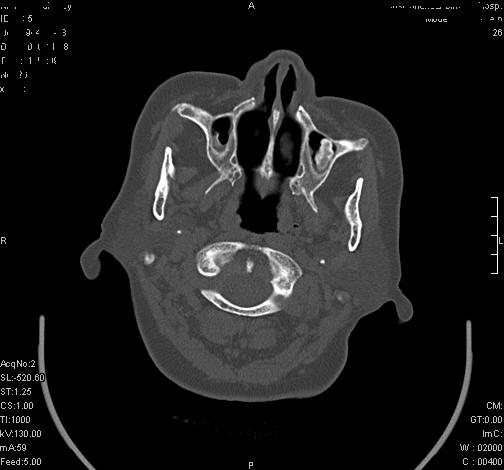

上次发的片子,不够细微。误导了大家,请大家再重新看一下,思路会更清晰。

双上颌窦高密度,其内见水样密度.考虑双上颌窦骨瘤伴上颌窦炎.

双上颌窦高密度,左侧病灶下部与左上颌窦底部骨质相延续,支持双上颌窦骨瘤

双侧上颌窦上部黏膜明显增厚、窦腔缩小,偏后侧窦壁骨质毛糙、模糊,窦腔内见条块状钙化。结合双侧鼻甲黏膜明显增厚,以及临床症状,

考虑:双侧上颌窦霉菌性鼻窦炎

双侧上颌窦密度增高,粘膜增厚,内见条片状钙化,窦壁无增生与破坏征象,双侧鼻甲粘膜肥厚.

意见:双侧霉菌性上颌窦炎.

温习:真菌性鼻旁窦ct特征 1)非侵袭性病变者可涉及到鼻腔和鼻窦,多为单侧,上颌窦最多见.2)ct示窦腔内软组织增生影,可呈息肉状,+c可强化3)增生软组织影内可见散在斑片状或沙砾状钙化区,此为其典型特点,4)

非侵袭性病变可见窦壁骨质增生,破坏少见;侵袭性病变可见窦壁骨质破坏.